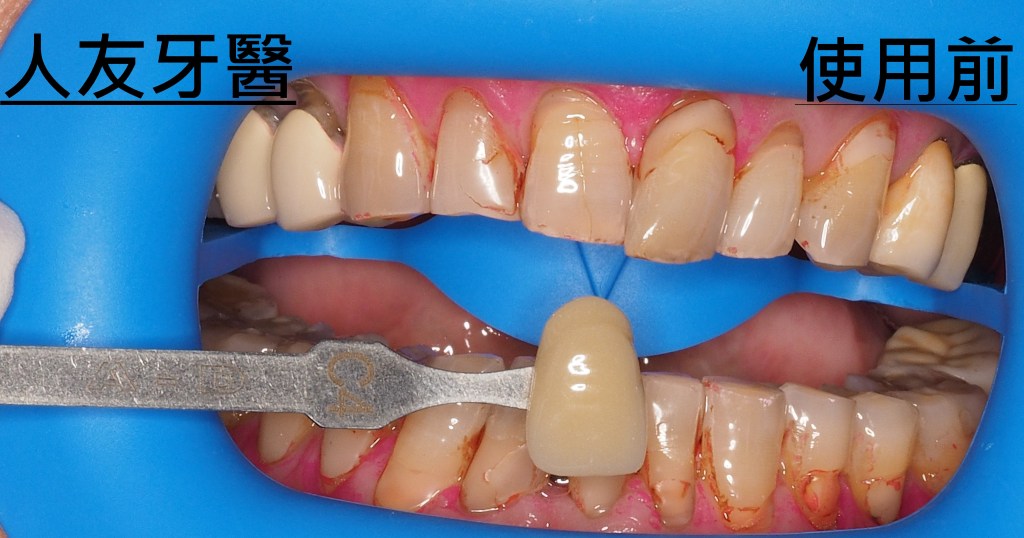

這位年輕女性患者的門牙和側門牙在別家治療半年,也有做四顆相連的牙橋,一直覺得很不舒服,笑起來不自然也不美觀,聽到鑽牙齒的聲音也很害怕。

下圖是別家做的牙橋

想詢問周醫師如何處理。醫師看了X-RAY發現右邊側門牙紅色圓圈的地方有病變,有可能留不住。左邊側門牙藍色箭頭牙齒有裂到肉,也可能留不住。經過討論後建議都拔除。